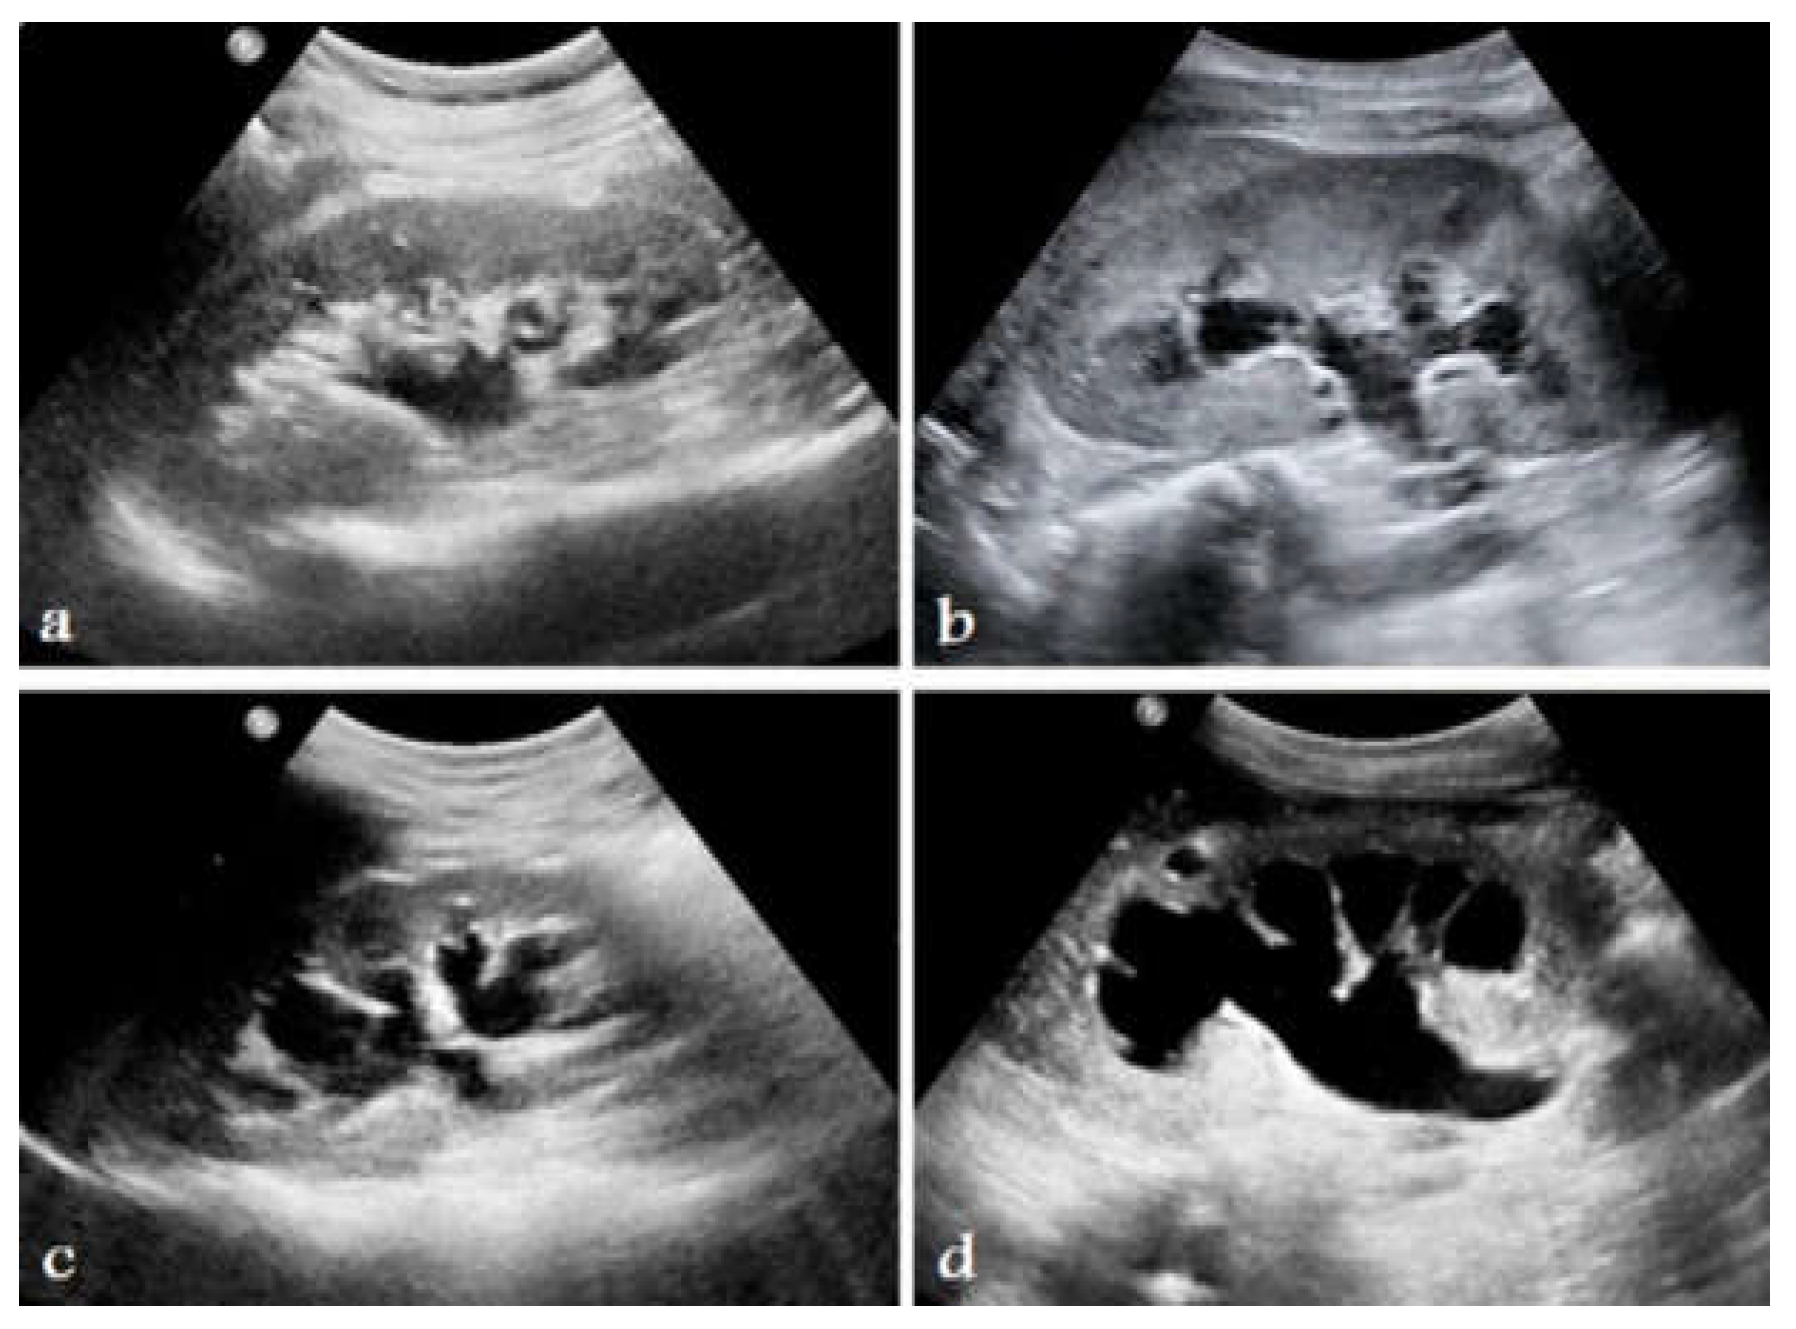

Figure 4. Kidney ultrasound scans indicating different levels of hydronephrosis: a) Grade-1, b) Grade-2, c) Grade-3, and d) Grade-4. Based on SFU grading system. [14].

Hydronephrosis is a medical condition that involves enlargement and distension of one or both kidneys due to accumulation of urine (Figure 3). Table 2 shows the challenges of managing hydronephrosis in pediatric urology, including the need for precise diagnosis and customized therapeutic approaches. Historically, evaluation of hydronephrosis has relied on subjective grading systems and intrusive diagnostic procedures, resulting in inconsistency in medical practice and possible hazards for patients. However, AI tools now offer promising alternatives to boost the precision of diagnoses, simplify clinical processes, and improve patient results. According to the Society for Fetal Urology (SFU) grading system, ultrasound scans can be used to determine hydronephrosis severity from Grade 1-4 (Figure 4).

Traditional methods of diagnosing pediatric hydronephrosis are limited by the subjective nature of ultrasound imaging and variability of interpretation [10]. Semi-quantitative ultrasonic analysis can result in observer-dependent outcomes, with a lack of explicit instructions for subsequent monitoring and management. In addition, establishing precise criteria for intervention based on grading methods such as the SFU [11] and the Urinary Tract Dilatation (UTD) [12] classification systems remain challenging. This ambiguity increases the need for invasive treatments, radiation exposure, and frequent testing, which places additional strain on young patients, their families, and healthcare systems [13].